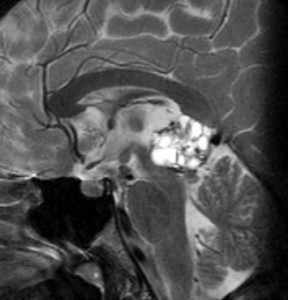

14歳の男の子です。このMRI画像はどう見ても松果体奇形腫 mature or immature teratoma 以外には考えられません。左の写真で脂肪腫が混じっていることが解ります。AFP 130 ng/ml, HCG-beta 30 mIUでしたから,ICE化学療法と放射線治療 (全脳室 25.2グレイ/15分割と局所28.8グレイ,1回線量1.8グレイ)をして少し小さくして(右の写真)から開頭手術しました。全摘出して病理診断は成熟奇形腫でしたが,治療前にはおそらくもっと未熟な部分が混じっていたと考えられます。